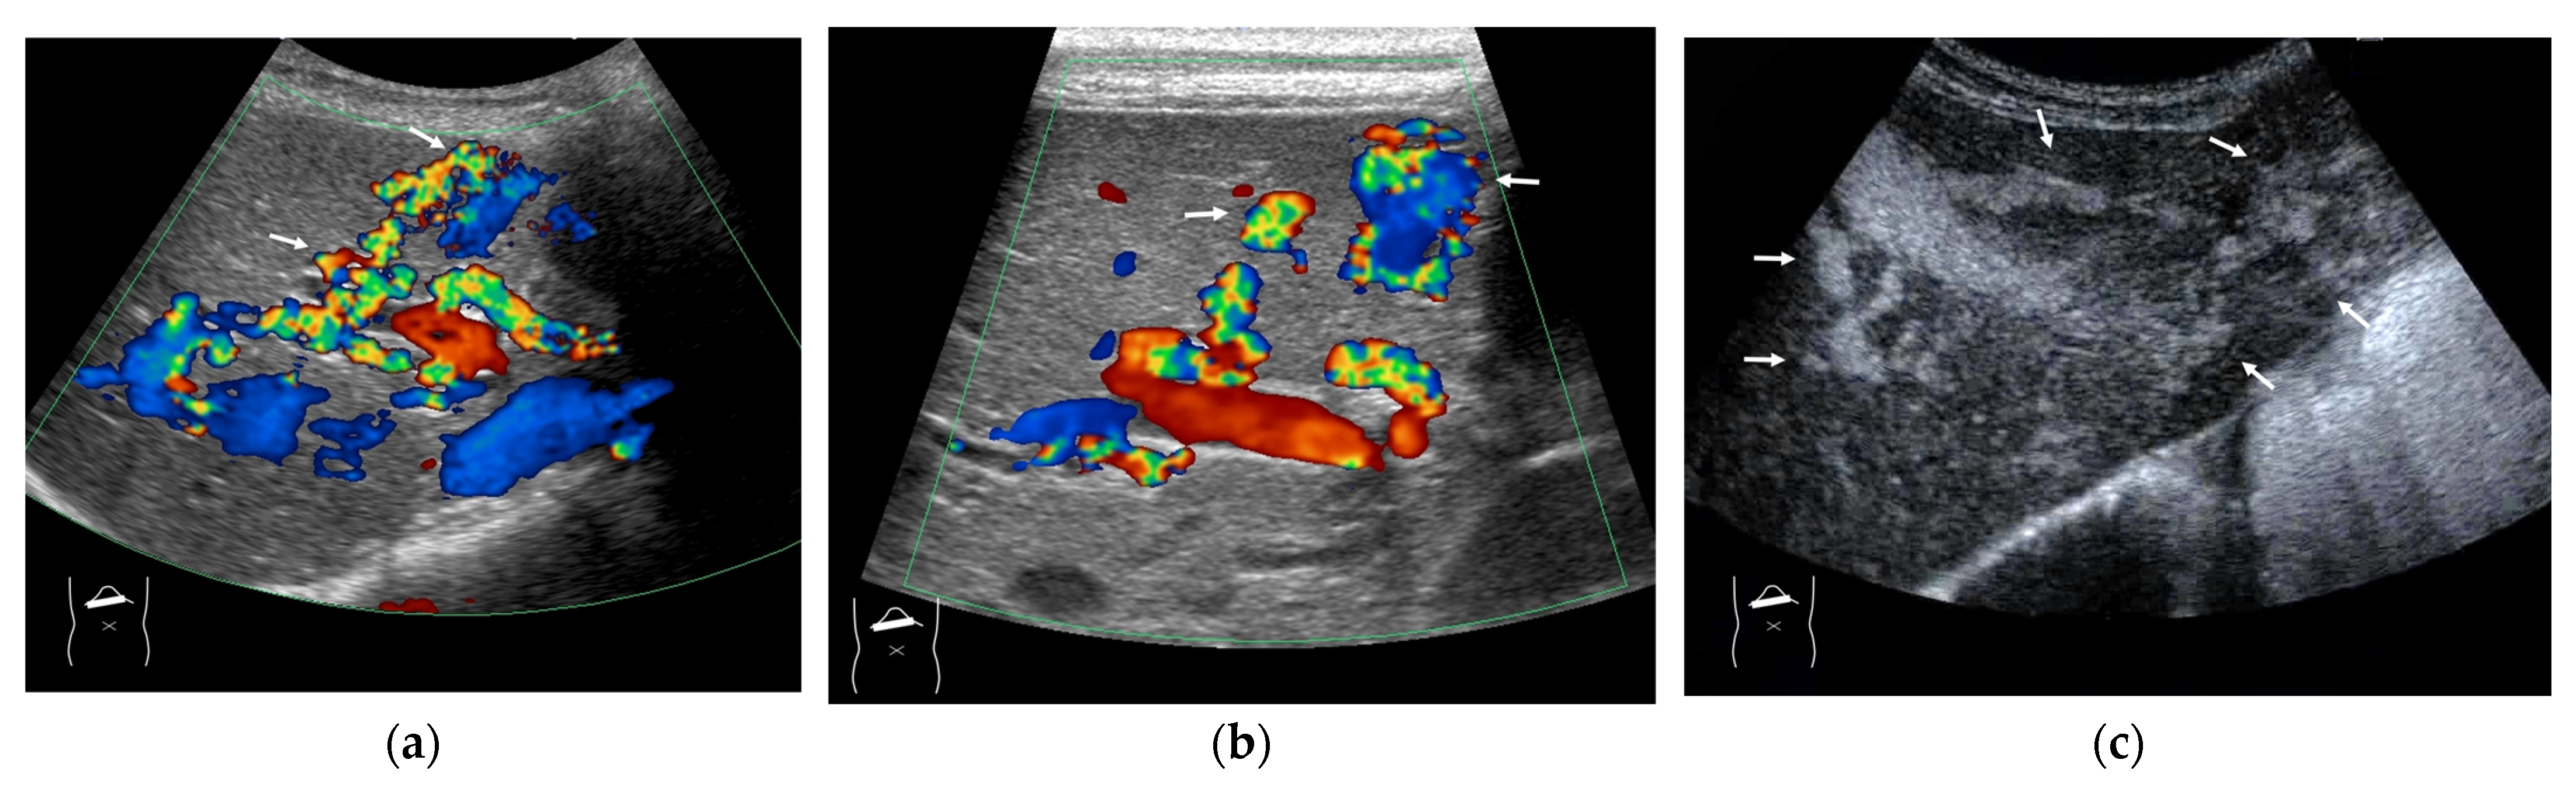

4.1. HHT-Related HV Abnormalities

Here, to understand these vascular shunts, we briefly discuss HHT. It is a multiorgan genetic angiodysplastic disease characterized by visceral vascular malformations and is diagnosed based on the Curacao criteria [46]. It affects not only the brain, lungs, gastrointestinal tract, and nasal mucosa, but also the liver [45,47]. It is well known that HHT produces many kinds of intrahepatic vascular shunts (Figure 8). Among these shunts, the A-V shunt is clinically the most important. The marked development of the A-V shunt results in ischemia and necrosis of the bile duct and portal vein wall due to stealing of arterial blood flow that is purposed to nourish the bile duct and portal walls. This leads to cholangitis, biloma, and liver abscess formation (Figure 9) [45,48]. More importantly, the increased blood flow draining into the cardiac system results in cardiac overload, which in turn induces chronic heart failure [45,49]. Of note is the fact that the development of each shunt is not even; therefore, the development of the A-V shunt also varies greatly among HHT individuals. From the diagnostic point of view, although color Doppler US can provide a rough image of intrahepatic vascular shunts, it is necessary to confirm whether the vessels in question are merely in close proximity to each other or whether a real shunt exists. CEUS facilitates this differentiation and the diagnosis of A-V shunts.

Figure 9.

Representative case of HHT with developed A-V shunts: (a,b) Color Doppler US reveals many dilatations of HA (arrows) and vascular shunts within the liver. (c) The presence of a large A-V shunt (arrows) is confirmed using CEUS.